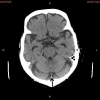

The author herein reports a large cell neuroendocrine carcinoma (LCNEC) of the lung diagnosed at a brain metastasis without clinical data. A 70-year-old man underwent esophagectomy for esophageal squamous cell carcinoma, and was treated with chemotherapy. At 72 years of age, he was found to have prostatic well differentiated adenocarcinoma, and treated by estrogen. At 78 years of age, he was pointed out to have gastric advanced tumor, and the biopsy showed moderately differentiated tubular adenocarcinoma. The gastric carcinoma was treated by chemotherapy. At 79 years of age, he was shown to have right lung shadow (2 cm in diameter) and brain shadow (cerebellar vermis) of 1 cm in diameter. Multiple biopsy and cytology of the lung failed to detect carcinoma cells. Biopsy of the brain was performed. The biopsy showed medullary undifferentiated carcinoma. Immunohistochemically, the tumor cells were positive for pancytokeratin AE1/3, synaptophysin, CD56 (NCAM), p53, Ki67 (labeling 40%), KIT and TTF-1, but were negative for vimentin, chromogranin, neuron-specific enolase and PDGFRA. A pathological diagnosis of metastatic LCNEC form the lung was made. A molecular genetic analysis for KIT (exons 9, 11, 13, and 17) and PDGFRA (exons 12 and 18) genes identified no mutations of the KIT and PDGFRA genes. The patients died of carcinomatosis one month after the diagnosis. In conclusion, careful histological and immunohistochemical examination can diagnose LCNEC of the lung at the metastatic site.